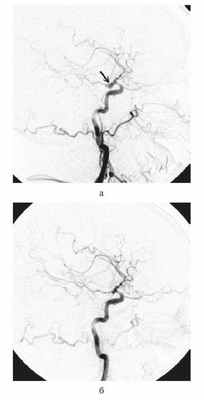

На следующий день (5-е сутки после САК) после стабилизации состояния пациентке была проведена операция — эндоваскулярная окклюзия аневризмы в области развилки правой ВСА микроспиралями (рис. 2).

Рисунок 2. Каротидная ангиограмма до операции (а). Аневризма развилки ВСА заднего расположения (указана стрелкой). Ангиографмма после окклюзии аневризмы микроспиралями (б). Больная перенесла операцию удовлетворительно, при ангиографии отмечено умеренное сужение артерий.